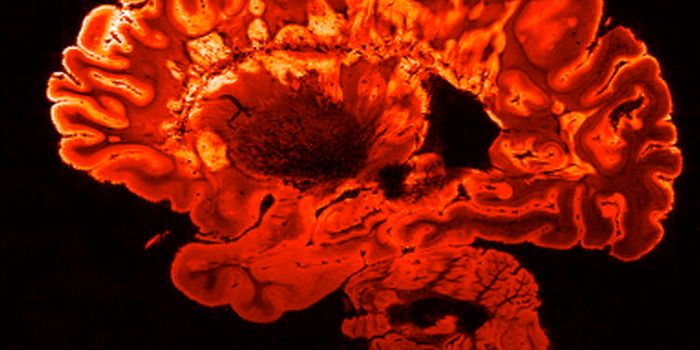

FEB 09, 2025CancerGlioblastoma (GBM), an aggressive form of cancer that grows in the brain or spinal cord, occurs at an incidence rate of ...